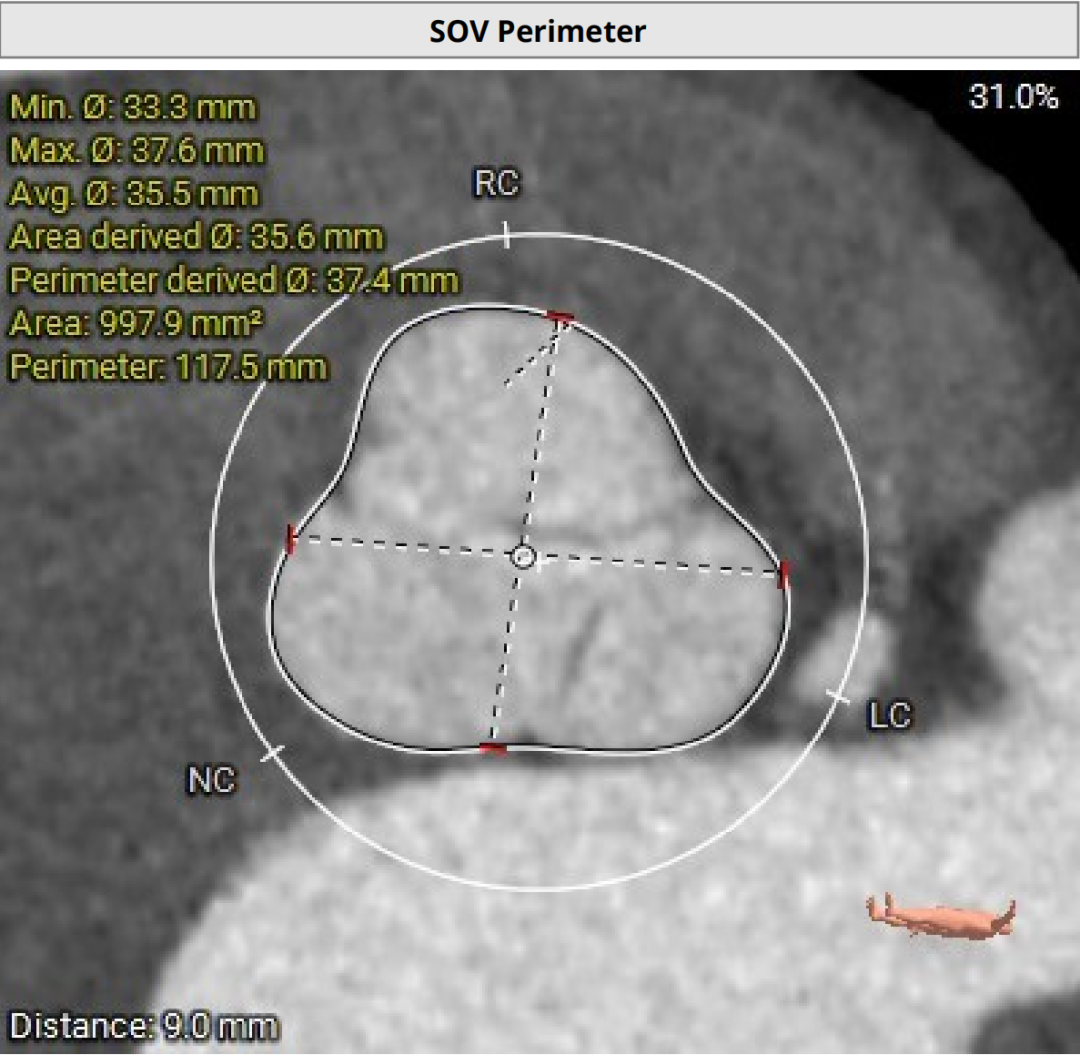

2026年伊始,TaurusTrio经导管主动脉瓣系统在复旦大学附属中山医院,浙江大学医学院附属第二医院,中国医学科学院阜外医院,首都医科大学附属北京安贞医院,四川大学华西医院等多家临床中心成功开展上市后全国首批植入。这不仅是TaurusTrio正式走向广泛临床应用的重要里程碑,更标志着中国单纯主动脉瓣反流介入治疗正式迈入了“心键合璧”的全新纪元。